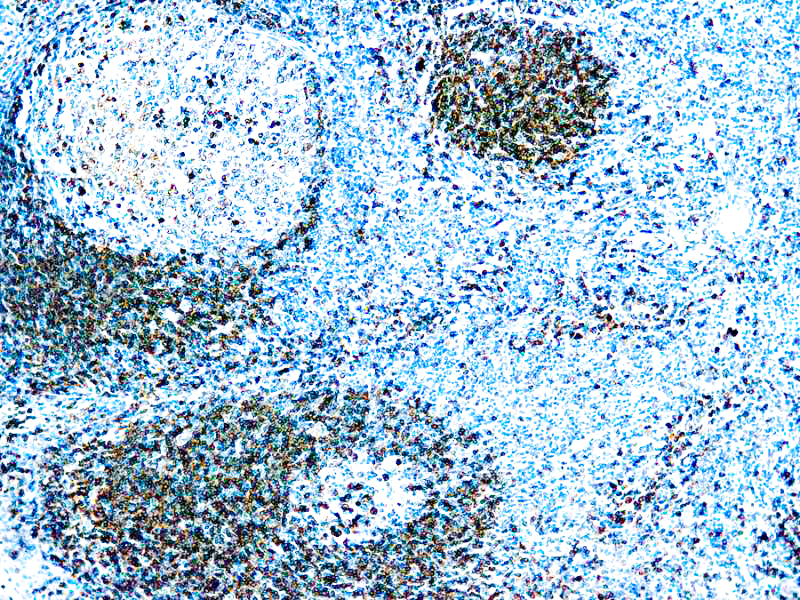

CD79a Antigen (HM47/A9)

This antibody is specific to human CD79a antigen complex, consisting of two polypeptides non-covalently associated with membrane-bound immunoglobulins on B cells. This complex of polypeptide and immunoglobulins constitute the B cell antigen receptor. The two components of this complex are designated CD79a and CD79b. The CD79a antigen appears at the pre-B cell stage, early in maturation and persists until the plasma cell stage. The CD79a antigen is found in majority of acute leukemias of precursor B cell type, in B cell lines and B cell lymphomas.

| Positive Control Tissue | Tonsil |